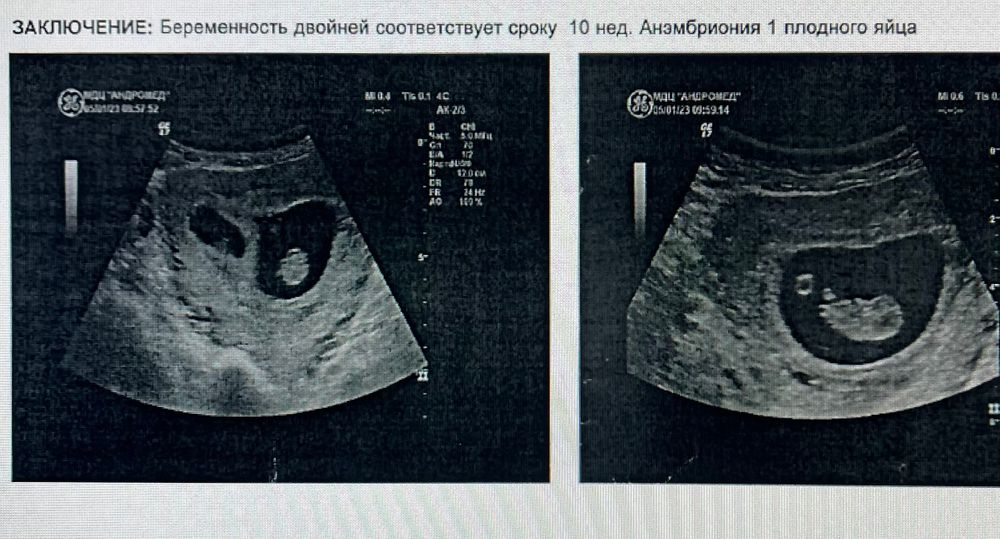

И на узи было так🤍🤍

Это такие эмоции! Хотелось и плакать и смеяться. Муж был удивлён не меньше меня. Погрузился в свои мысли и просто порхал от счастья.... было узи через неделю-и тот же результат-появились эмбрионы -двойня))) Муж уже выбрал коляску для двойни и начал выбрить кроватку...

Потом было ещё узи и увы остался только один(((😭

Так часто бывает...

Первый скрининг подтвердил самопроизвольную редукцию одного эмбриона. Генетик сказала, что возможно с моей анемией это и к лучшему... Но нам было не легче от этих слов.. грустно и сейчас😥